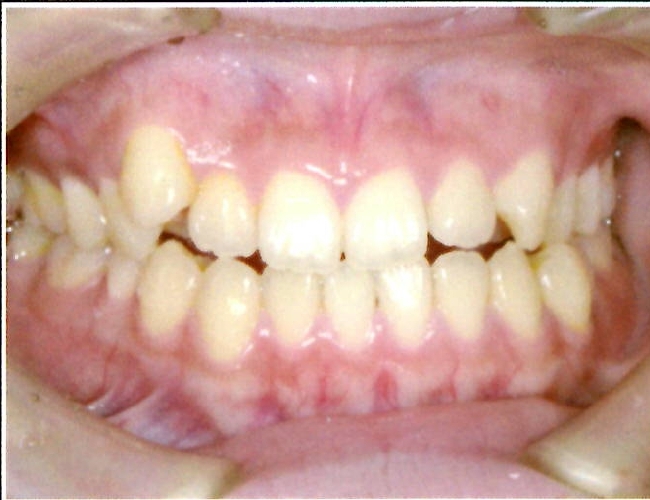

| 主訴・治療前の状態 | 過蓋咬合(噛み合わせが深く、下の前歯が見えない状態)により歯ぎしりができない状態でした。また、上下顎前歯部に叢生(クラウディング・ガタガタ)がありました。 |

| 治療内容 | 矯正治療により、過蓋咬合と上下の叢生を改善しました。 |

| 治療結果 | 適切な被蓋(上下の前歯の重なり)が得られ、下の前歯がきちんと見えるようになりました。上下の前歯の歯並びも美しく整い、しっかりと噛み合うようになりました。機能面・審美面ともに大きく改善した症例です。 |